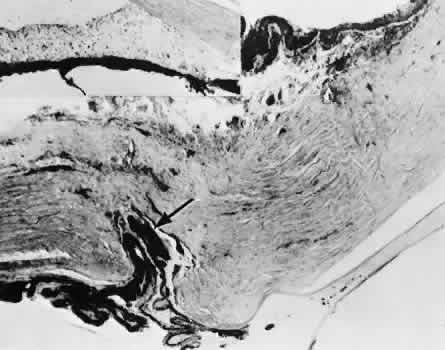

Descemet's membrane is only loosely adherent to the posterior stroma and may be stripped into the anterior chamber at the time of the corneal incision placement (Fig. 27) or injection of sodium hyaluronate. Splitting off of Descemet's membrane from the posterior cornea can lead to postoperative intractable corneal edema.89,90

Fig. 27. A case of stripping of Desce-met's membrane during a filteringprocedure (scleral cautery and iridectomy). A. The clinical appearance was one of extensive filtering bleb formation superiorly and regional dense corneal edema and opacification. B. The anterior chamber remains formed. Detached Descemet's membrane can be seen protruding into the anterior chamber. The patient died shortly after surgery from unrelated causes.C. The gross appearance of the area of detached Descemet's membrane extending into the anterior chamber.D. On the histologic section, the origin of detached Descemet's membraneextends to the region of the limbal wound. (Hematoxylin-eosin stain; × 16.) (Kozart DM, Eagle RC Jr: Stripping of Descemet's membrane after glaucoma surgery. Ophthalmic Surg 12:420–423, 1981.)